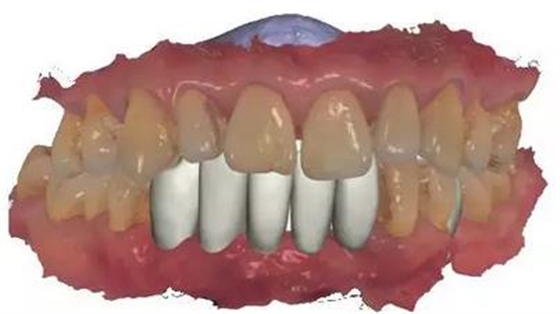

▲女性,42歲,牙周病,下前牙固定不良修復(fù)體,基牙炎癥、松動(dòng)。

▲拆除不良修復(fù)體,拔除松動(dòng)牙

▲下前牙數(shù)字化導(dǎo)板引導(dǎo)下種植后即刻修復(fù),6顆缺失牙,擬種植3-4顆

▲雙側(cè)上后牙暫不修復(fù)。

初診時(shí)下前牙不良修復(fù)體

去除不良修復(fù)體后鄰牙松動(dòng)

通過3shape trios口內(nèi)掃描儀掃描數(shù)據(jù)。

利用3shape導(dǎo)板軟件虛擬排牙

以修復(fù)為導(dǎo)向規(guī)劃植體

牙支持式導(dǎo)板生成

通過3Shape Dental System軟件同期設(shè)計(jì)臨時(shí)冠

手術(shù)導(dǎo)板數(shù)據(jù)發(fā)送至成都登特,通過BEGO打印機(jī)打印出導(dǎo)板,切削出臨時(shí)冠

導(dǎo)板就位后逐級(jí)擴(kuò)孔

臨時(shí)冠就位,即刻修復(fù),無咬合接觸

修復(fù)后全景片

總結(jié)

1:本病例的難度在于高骨密度

的條件下如何順利植入植體

2:數(shù)字化修復(fù)時(shí),

種植臨時(shí)修復(fù)體可能難以就位,

特別是多顆牙的修復(fù)

來源:滿毅副教授